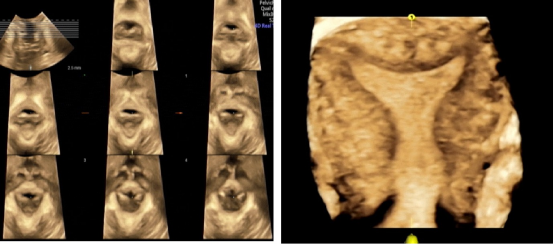

三节段分析法精准诊断胎儿唇腭裂

通过上唇、上牙槽突及继发腭三个节段有序联合,判断胎儿唇腭的发育情况,精确诊断胎儿唇裂畸形。

盆底及子宫三维超声

子宫三维超声通过透明成像、表面成像、多平面成像、三维彩超重建等技术,清晰显示病变情况,直观显示病变部位与周围组织关系。

盆底三维超声:在全市率先开展了盆底三维超声,首创了应用阴道气体线诊断子宫脱垂,既能静态观察盆底解剖结构,还能动态评估盆底功能的优点,为广大女性的盆底健康提供有力护航。